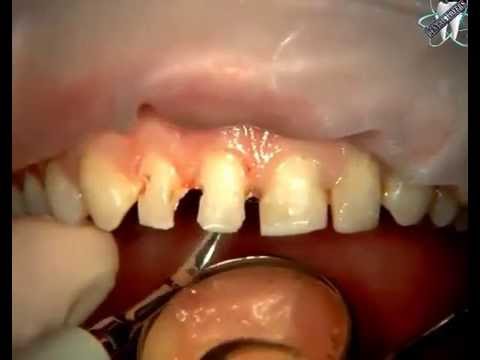

home Aesthetics Aesthetic anterior restoration Demonstration Aesthetic anterior restoration Demonstration By dentists Posted in Aesthetics Posted on June 26, 2017